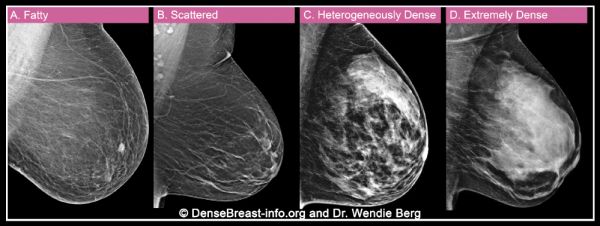

其次X线检查中,致密乳腺可能会掩盖癌症病灶,增加漏诊风险。有数据显示,在极度致密型乳腺中,大约有40%的乳腺癌在X线检查中是看不到的。

如该动图所示,乳腺密度越大,X线检查中癌症病灶被掩盖的风险就越高。丨DenseBreast-info.org and Dr. Wendie Berg